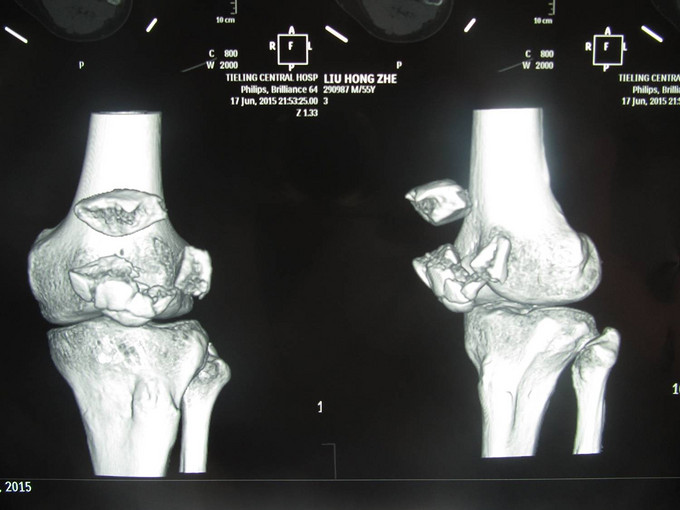

患者自诉于2015年5月17日晚21点多在外不慎摔伤,致左膝部疼痛肿胀活动受限,当时无意识不清,急诊送当地医院(铁岭市中心医院),行左膝关节DR及三维CT:左髌骨骨折。今为进一步治疗急于我院中国医科大学附属盛京医院,行X线片检查示:左髌骨骨折,急诊以“左髌骨骨折”为诊断收住入院。

诊断:左髌骨骨折 患者入院后左膝部抬高,冷疗,消肿等对症治疗后,约一周后行左髌骨骨折切开复位张力带内固定术。